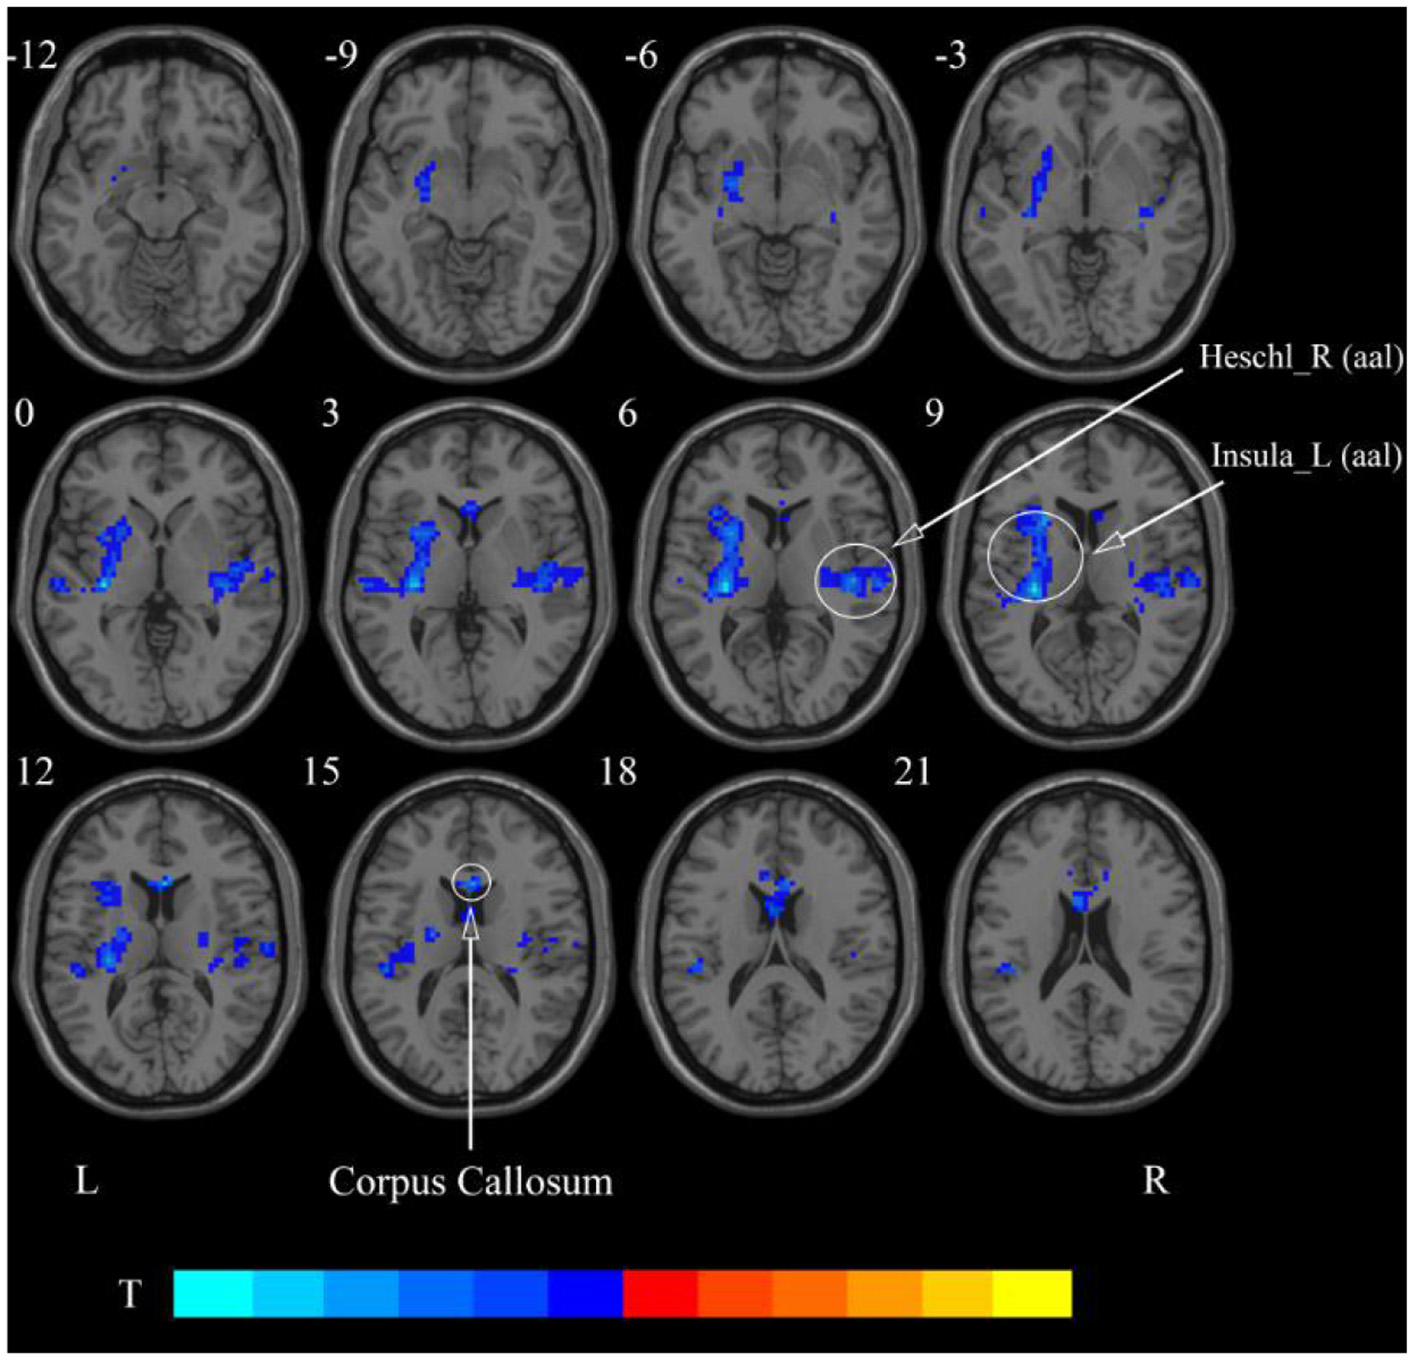

After cerebellar stimulation, in the classical frequency band we found significantly decreased ReHo at the left insula, right temporal lobe, and corpus callosum (p < 0.05; Figure 6 and Table 2). In addition, a decrease in ReHo was also found at the left insula and corpus callosum in the slow-4 band and at the right temporal lobe, left putamen, and left motor accessory area in the slow-5 band (p < 0.05; Figures 7, 8 and Table 2).

Figure 6. Statistical maps showing ReHo change pre- and post-rTMS in the classical frequency band. Cool colors showing ReHo decreased after rTMS p < 0.05.